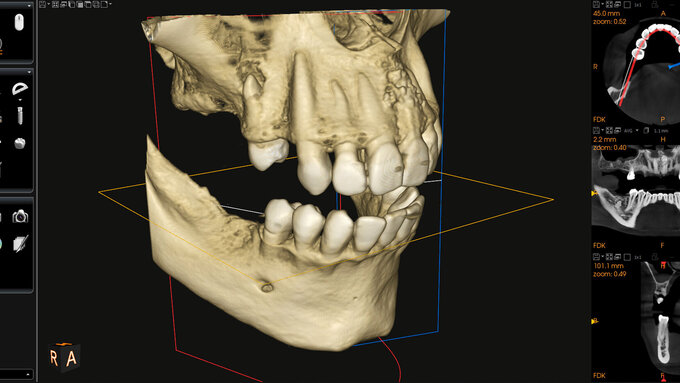

Zaghden et al. erklären, dass DVT-Aufnahmen als Goldstandard für die sichere Diagnosestellung von atherosklerotischen Gefäßveränderungen gelten – auch wenn diese nicht standardmäßig dafür verwendet werden. Die Zuverlässigkeit einer PSA ist im Vergleich geringer. In der Literatur werden Sensitivitäten von 31 bis 100 Prozent angegeben, berichten die Autoren. Grund dafür könnten zum Beispiel Überlagerungen, eine zu geringe Größe der Plaques oder zu geringe Verkalkung, die Geräteeinstellung oder die nicht korrekte Positionierung des Patienten sein. Auch die Erfahrung des Zahnarztes oder der Zahnärztin spielt keine unerhebliche Rolle, da die A. carotis nicht im Fokus der Befunderhebung steht. Nicht alle in der PSA entdeckten Verkalkungen spiegeln eine signifikante Stenose wider, sollten aber in jedem Fall kardiologisch abgeklärt werden.